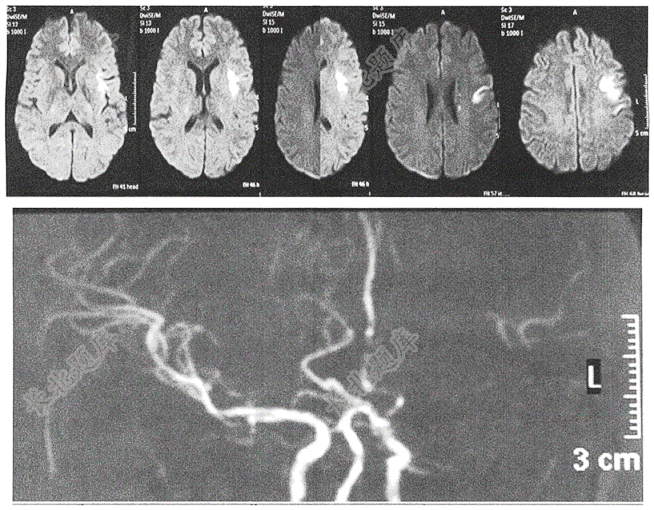

- 单项选择题老年女性患者,因“右侧肢体无力5天”为主诉入院。MRI-DWI及MRA结果如图所示。患者最可能的诊断是( )

A、脑出血,颅内血管畸形

B、脑梗死,小动脉闭塞型

C、脑梗死,心源性栓塞

D、脑梗死,大动脉粥样硬化型

E、脑出血,大动脉粥样硬化